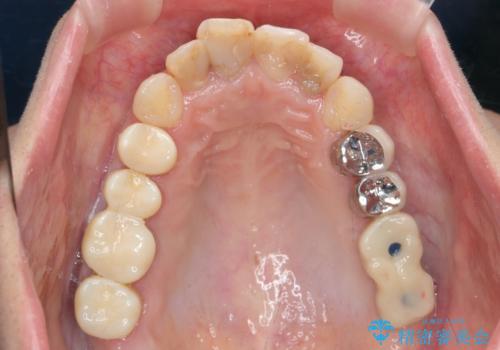

インプラント・セラミック・矯正治療を含む包括歯科診療

- 20代女性

虫歯や咬合関係・歯槽骨の吸収・根尖病変・歯の欠損・複合的な問題を一つずつ解決し、

安定した噛み合わせの構築・歯ブラシのしやすい環境の整備・歯内歯周の感染除去・造骨を伴うインプラント治療

を行い、長期的な予後を見込める口腔内環境を確立、整備して行きます。